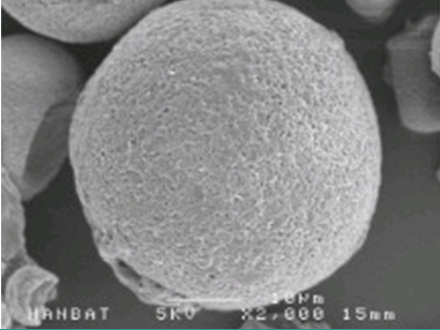

입자의 크기가 작아 일반적으로 사용되는 바늘보다

훨씬 가는 바늘로 시술이 진행되며, 녹는 시간이 빠르고 균일한 편입니다.